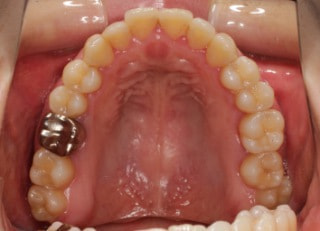

治療前

検査時パノラマレントゲン

全体の歯根のパラレリング(平行性)は悪い状態ではありません。顎関節の変形などはありません。鼻閉もありません。

成人の反対咬合なので、少し顎関節にダメージはありますが、重症ではありません。CO(中心咬合位)の位置には問題があります。CO-CRのズレが存在しますので、顎関節には負担がかかっています。